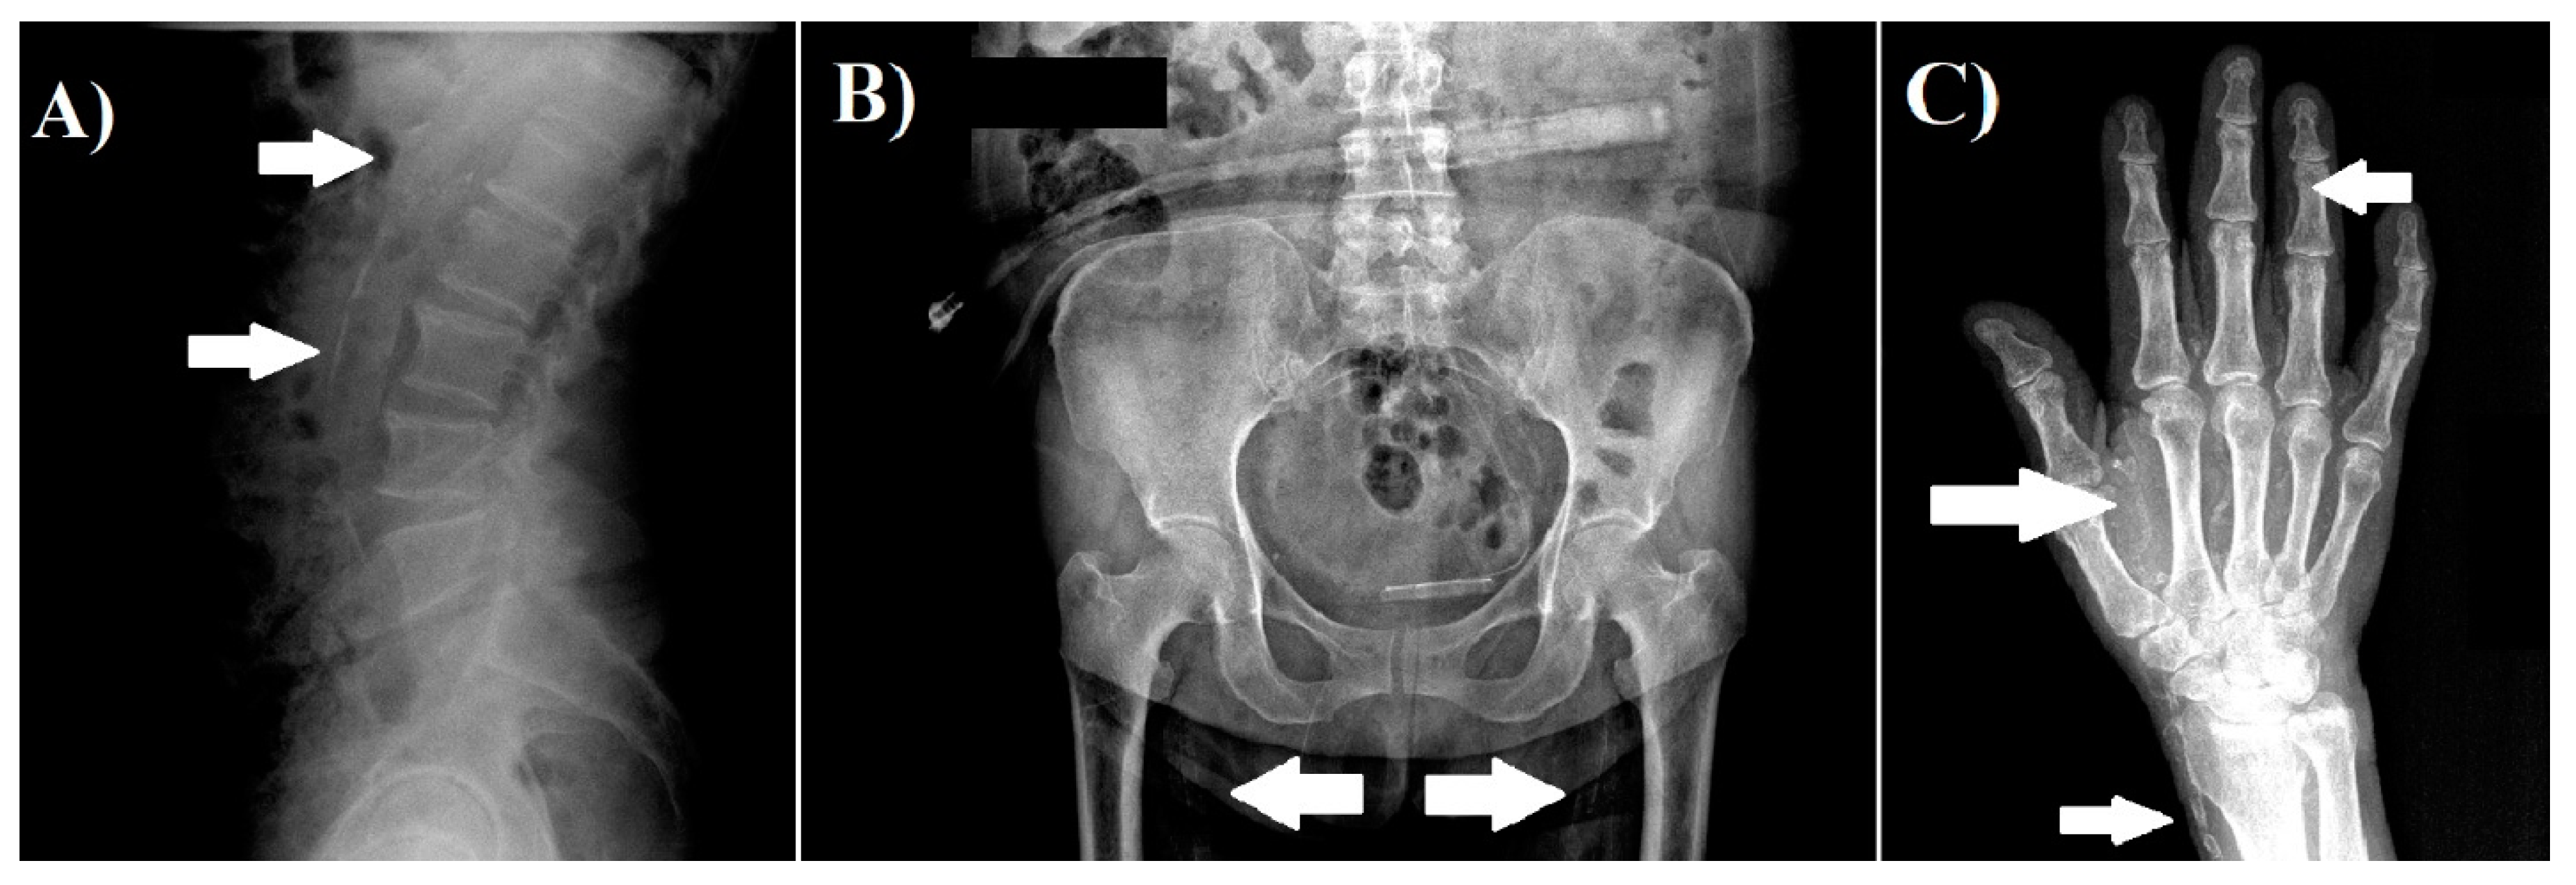

2.3. Vascular Calcification Assessment

- Adragao, T.; Pires, A.; Lucas, C.; Birne, R.; Magalhaes, L.; Gonçalves, M.; Negrao, A.P. A simple vascular calcification score predicts cardiovascular risk in hemodialysis patients. Nephrol. Dial. Transpl. 2004, 19, 1480–1488. [Google Scholar] [CrossRef] [Green Version]

- Gan, L.Y.; Wang, M.; Yu, X.Y. Application of plain radiography for diagnosis of vascular calcification in maintenance hemodialysis patients. Chin. J. Nephrol. 2009, 2, 81–85. [Google Scholar]